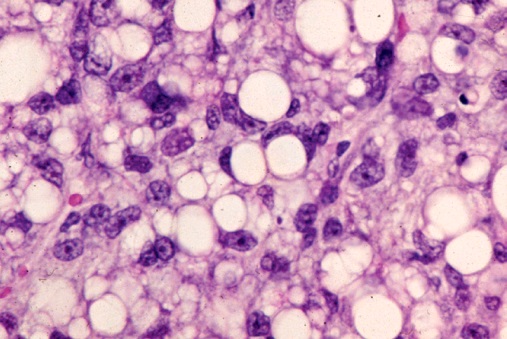

Липосаркома у собак и кошек - перевод из Small Animal DERMATOLOGY veter96.ru

ОнкоВет: Липосаркома у кошки

Липосаркома у собаки породы кане-корсо Гистология Второе мнение